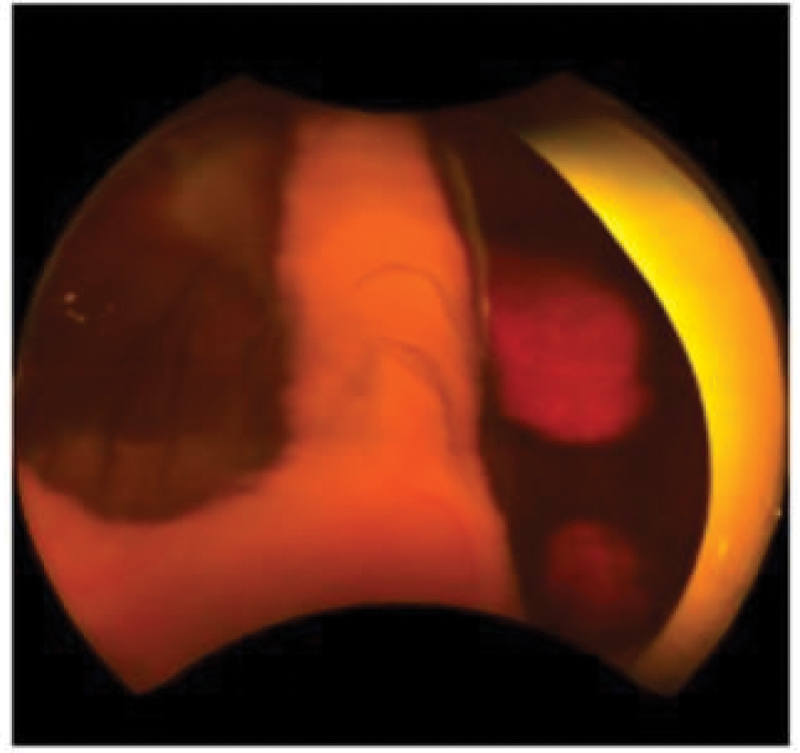

Background: Retina fundus images conducted in Greenland are telemedically assessed for diabetic retinopathy by ophthalmological nurses in Denmark. Applying an AI grading solution, in a Greenlandic setting, could potentially improve the efficiency and cost-effectiveness of DR screening.Method: We developed an AI model using retina fundus photos, performed on persons registered with diabetes in Greenland and Denmark, using Optos® ultra wide-field scanning laser ophthalmoscope, graded according to ICDR.Using the ResNet50 network we compared the model's ability to distinguish between different images of ICDR severity levels in a confusion matrix.Results: Comparing images with ICDR level 0 to images of ICDR level 4 resulted in an accuracy of 0.9655, AUC of 0.9905, sensitivity and specificity of 96.6%.Comparing ICDR levels 0,1,2 with ICDR levels 3,4, we achieved a performance with an accuracy of 0.8077, an AUC of 0.8728, a sensitivity of 84.6% and a specificity of 78.8%. For the other comparisons, we achieved a modest performance.Conclusion: We developed an AI model using Greenlandic data, to automatically detect DR on Optos retina fundus images. The sensitivity and specificity were too low for our model to be applied directly in a clinical setting, thus optimising the model should be prioritised.

Abstract Image